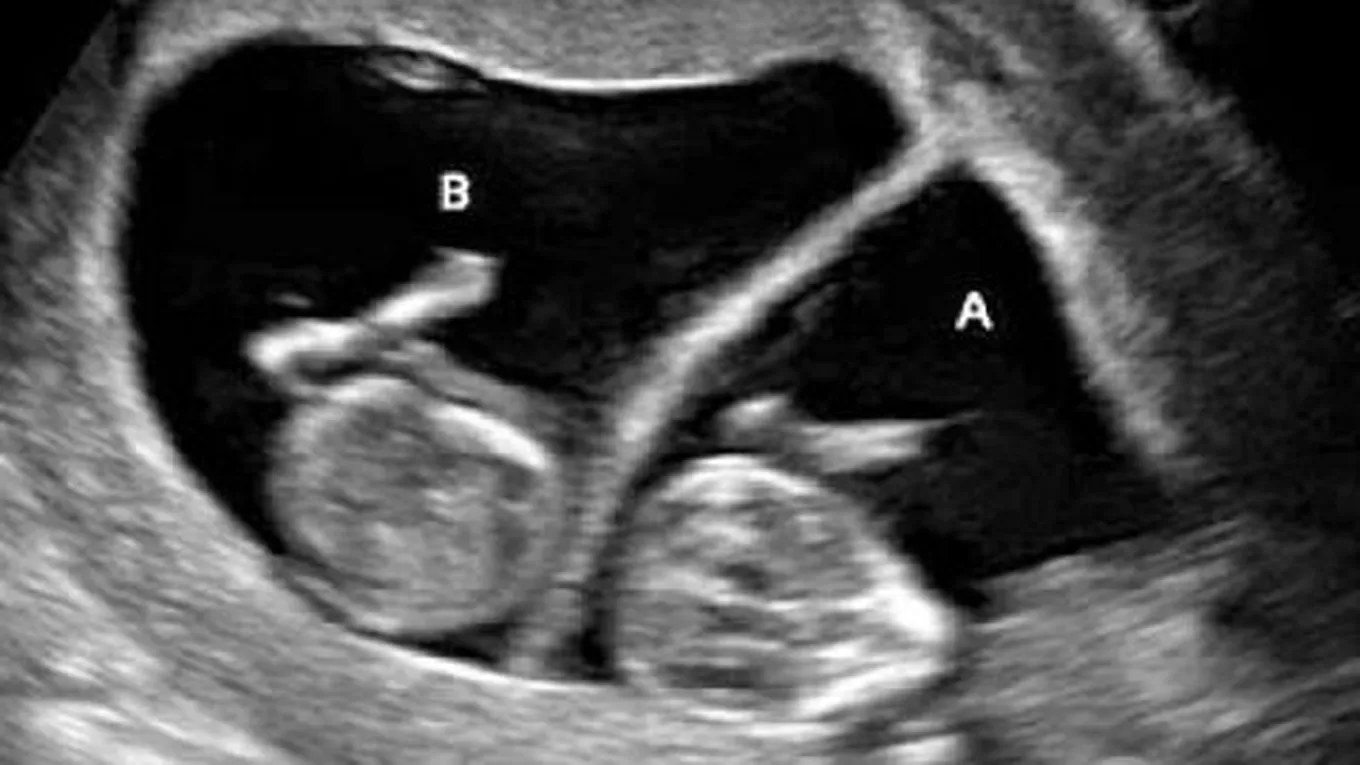

يحدث الحمل عادةً بعد انتهاء الحيض بأسبوعين، ويستمر لمدة تسعة أشهر، تمر خلالها الأم وطفلها بالعديد من التغيرات الجسمية والنفسية، حيث تبدأ هذه المرحلة بالتقاء الحيوان المنوي الذكري مع البويضة الأنثوية لتشكيل البويضة المخصبة التي تنمو مع الأيام لتصبح جنيناً، ولكن أحياناً قد تنقسم هذه البويضة إلى قسمين أو أكثر لينمو في رحم الأم ما يعرف باسم التوأم، وفي هذا المقال سنعرفكم على مراحل تكون الجنين التوأم بشكلٍ مفصل.

- تُزرع البويضة في جدار الرحم، حيث تبدأ خلاياها بالانقسام لتكوين الأجنة، وفي هذه الحالة إما تنقسم البويضة إلى خليتين متماثلتين ينتج عنهما توأم متطابق (إما بنتان أو ولدان)، أو أن تُخصَّب بويضتان في الوقت نفسه وبشكلٍ منفصل، الأمر الذي ينتج عنه توأم غير متطابق.